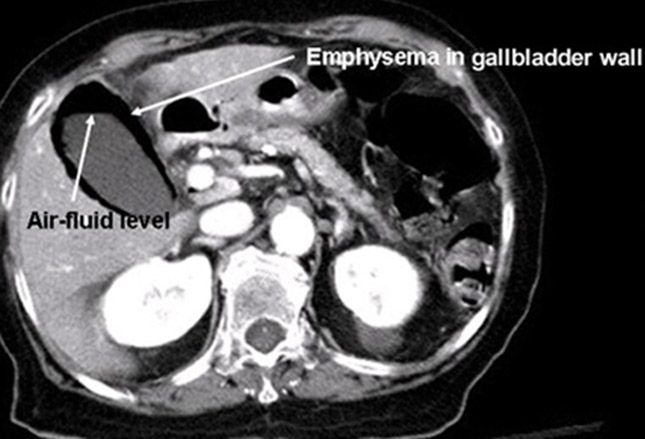

答案:D.乙状结肠扭转

通过CT检查

,可以看见近端结肠正常表现,乙状结肠扩张(如下图箭头所示)。长期卧床患者和精神障碍患者的风险最大,因为精神药物可以减缓肠道蠕动。冗余乙状结肠(乙状结肠延伸,导致一个冗余环路)也是风险因素。患者一般表现为急性腹痛

、痉挛、腹胀和便秘。

通过静脉(IV)输液和广谱抗生素使用,患者病情初步稳定。对病情不稳定的患者,手术是最佳疗法,但对病情稳定的患者,内镜减压可能是合适的初始方案。